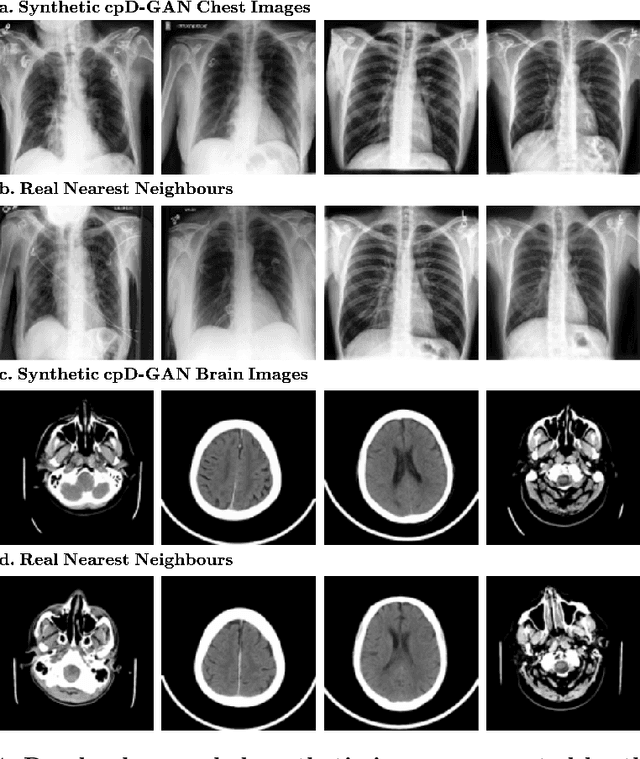

Abstract:Privacy concerns around sharing personally identifiable information are a major practical barrier to data sharing in medical research. However, in many cases, researchers have no interest in a particular individual's information but rather aim to derive insights at the level of cohorts. Here, we utilize Generative Adversarial Networks (GANs) to create derived medical imaging datasets consisting entirely of synthetic patient data. The synthetic images ideally have, in aggregate, similar statistical properties to those of a source dataset but do not contain sensitive personal information. We assess the quality of synthetic data generated by two GAN models for chest radiographs with 14 different radiology findings and brain computed tomography (CT) scans with six types of intracranial hemorrhages. We measure the synthetic image quality by the performance difference of predictive models trained on either the synthetic or the real dataset. We find that synthetic data performance disproportionately benefits from a reduced number of unique label combinations and determine at what number of samples per class overfitting effects start to dominate GAN training. Our open-source benchmark findings also indicate that synthetic data generation can benefit from higher levels of spatial resolution. We additionally conducted a reader study in which trained radiologists do not perform better than random on discriminating between synthetic and real medical images for both data modalities to a statistically significant extent. Our study offers valuable guidelines and outlines practical conditions under which insights derived from synthetic medical images are similar to those that would have been derived from real imaging data. Our results indicate that synthetic data sharing may be an attractive and privacy-preserving alternative to sharing real patient-level data in the right settings.